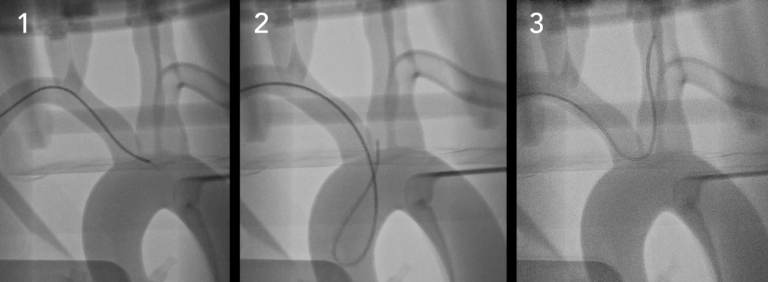

●具有清晰视野的多种成像模式– CT,荧光检查和照相机

●执行EVAR,TEVAR,FEVAR,TAVR等

四、提供各种可定制硅胶血管:

可以根据患者的te定扫描或设计(CT,MRI,3DRA,STL)定制各种血管解剖结构。 这允许用户复制各种程序来训练或开发设备,例如分流器,支架取回器,线圈,支架移植物和其他新型设备。

这些解剖结构包括但不限于主动脉和胸主动脉瘤,中风,脑动脉瘤和AVM,主动脉瓣疾病等。 可根据要求对容器的几何形状以及厚度和润滑涂层进行进一步修改